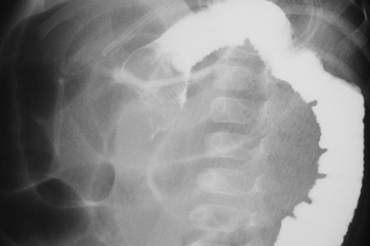

Invaginación Intestinal